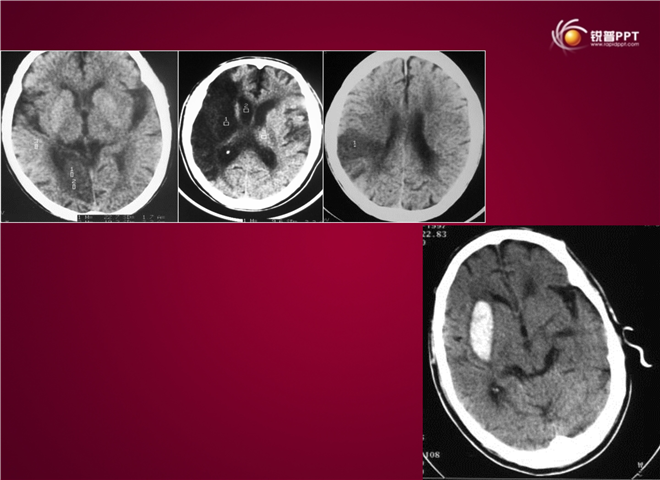

23_CT读片基础